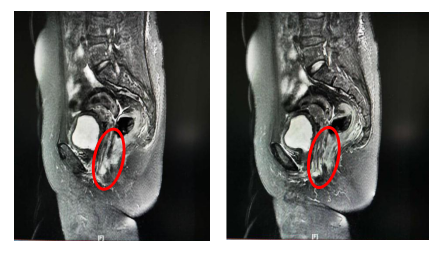

MRI:病变直径缩小1cm,肿瘤体积减少约50%

查体:阴道肿瘤消退,阴道壁光整部分弹性恢复,右后侧壁局限性深溃疡形成;直肠右前侧壁可触及凹陷。

盆腔MRI提示:阴道肿瘤侵犯直肠